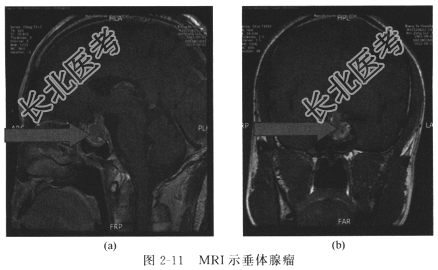

患者,女,36岁,因面容改变、四肢肢端肥大2年,头痛6个月,视力下降、视物模糊1个月入院。患者2年前无诱因出现嘴唇肥厚,鼻增宽,颜面部增大,四肢肢端肥大。无头痛,无视力、视野障碍,无闭经、泌乳,患者未予重视,未做处理。6个月前无明显诱因出现间断头痛。1个月前患者突发视力下降、视物模糊,为求进一步诊治入住我科。患者自起病以来无高热及抽搐发作,无恶心、呕吐,精神、食纳一般,大小便正常。既往体健,否认传染病及家族性疾病史,无药物及食物过敏史。护理体查T36.8℃,P78次/分,R20次/分,BP121/78mmHg,意识清楚,言语流利,定向力、理解力、记忆力未见明显异常。鼻腔及外耳道无异常分泌物,双侧嗅觉正常。双瞳孔等大等圆,直径约2mm大小,对光反射灵敏,眼球活动可,无眼睑下垂,视力粗测左眼0.5、右眼0.6,视野检查双颞侧偏盲。口唇肥厚,颜面部增宽,鼻宽大,面部感觉正常,额纹对称,鼓腮示齿时口角无歪斜。粗测听力正常,无饮水呛咳、吞咽困难。四肢肢端肥大,活动可,肌力正常,浅反射及腱反射正常,未引出病理反射。心、肺、肝等其他部位未见异常。辅助检查MRI显示鞍区肿瘤,向上突入鞍上池,压迫视交叉(图2-11)。内分泌检查垂体六项提示生长激素(GH)8μg/L。